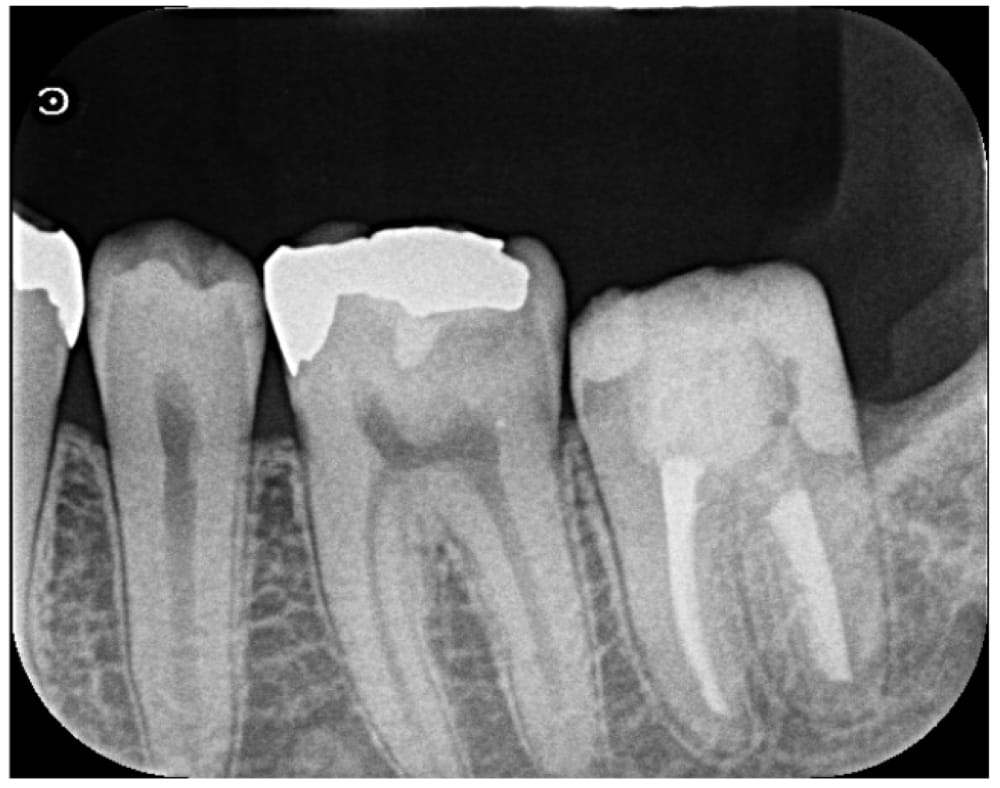

下顎第二大臼歯(7番)の遠心側(後方)に、大きな虫歯が広がっていることが確認できました。歯髄検査の結果からも、一部神経は強い炎症を起こしている状態です。歯髄保存療法で重要なことは、虫歯を完全に除去し、その上で唾液の侵入を防ぎ、歯髄に対する精密な処置を行うことにあります。今回の状態は、虫歯が非常に深い位置に進んでおり、歯髄保存療法を行うことは難しいと判断し、根管治療を実施しました。

根管治療後から特に痛みはなく、良好な経過をたどっています。レントゲンでも根尖部の病変の出現は認められず、治癒傾向ありと判断し、最終補綴(クラウンによる被せ物)へ移行することになりました。